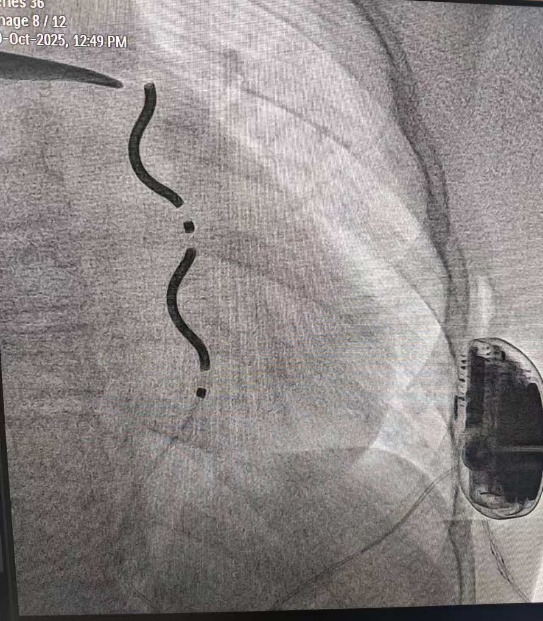

10月29日上午,心胸外科、心血管内科、麻醉科等多科室专家协同作战,为辰辰实施EV-ICD植入手术。术中,团队通过胸骨下方的微小切口,将专用血管外除颤导线精准植入胸骨后间隙,再与埋在左侧腋下的除颤器主机连接。这种导线系统完全避开心脏和血管,依靠胸骨后贴近心脏的解剖位置,实现对心律失常的监测与治疗。

术中植入EV-ICD后的图像

手术中,团队按标准程序进行严格系统测试:通过程序电刺激诱发出持续性室性心动过速,EV-ICD系统即刻准确识别,并成功实施转复治疗。测试数据显示,该系统心律失常识别灵敏度达100%,除颤效能与经典经静脉ICD相当,各项参数均符合临床预期。手术仅用一个多小时,流程顺畅,术后辰辰生命体征平稳,顺利返回普通病房。此次手术的成功,不仅挽救了辰辰的生命,也为我国儿童心脏猝死预防领域的技术创新增添了重要一笔。